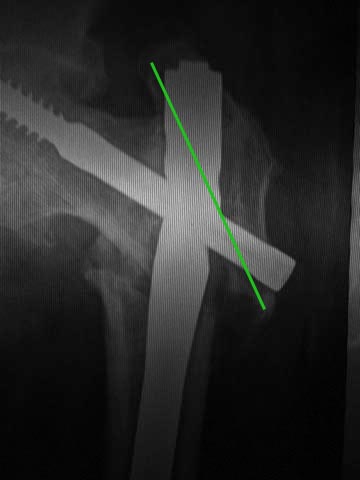

Про динамизацию забыли написать. Но проблема из без нее очевидна. Типичная

ошибка с "диагональным" положением гвоздя. Т.е. латеральная точка введения

и направление к медиальной стенке центрального отломка. Как он должен бы

располагаться - зеленая линия на картинке. Соответственно, надо

пересинтезировать аналогичным имплантатом, не повторив этой ошибки.

Наверно, можно в шейку в передне-заднем направлении ввести 1-2 винта в

проекции канала от lag screw.